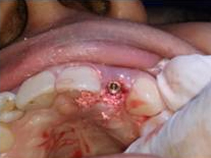

Implant with bone Graft

Placement of Bone Grafting

Suturing done